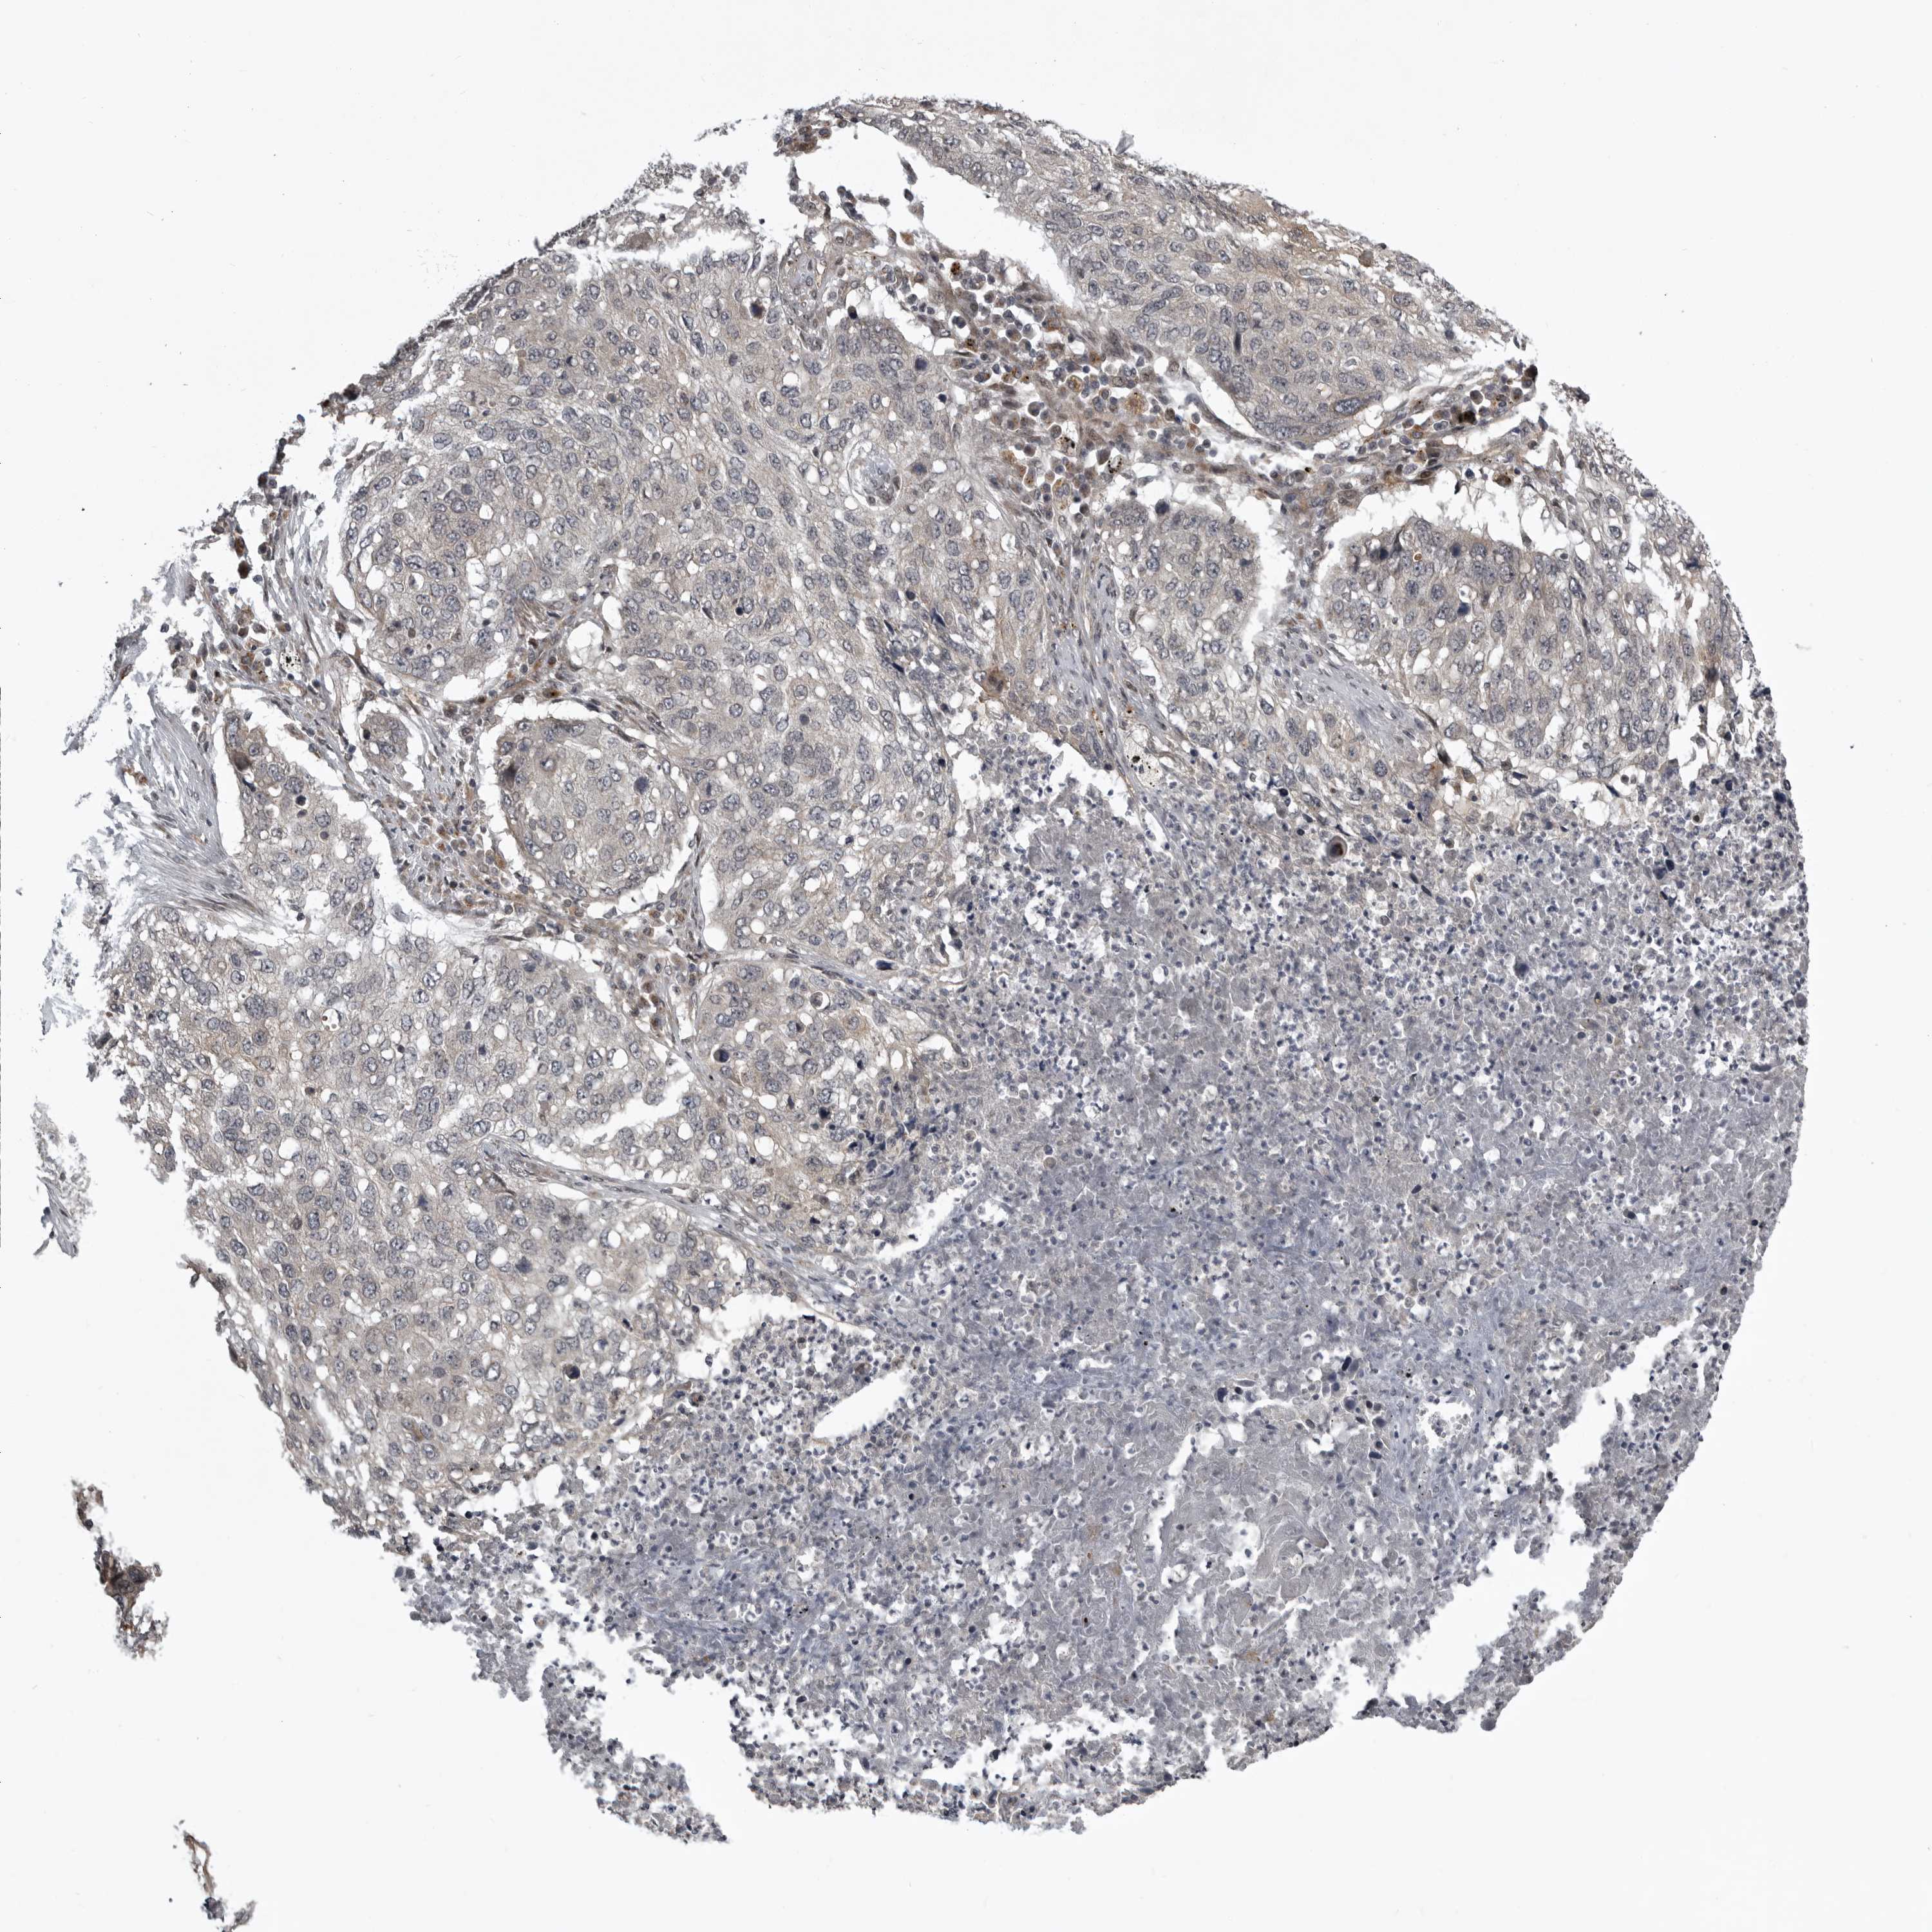

LUNG SQUAMOUS CELL CARCINOMA (TCGA) - Interactive survival scatter ploti

The Survival Scatter plot shows the clinical status (i.e. dead or alive) for all individuals in the patient cohort, based on the same data that underlies the corresponding Kaplan-Meier plots. Patients that are alive at last time for follow-up are shown in blue and patients who have died during the study are shown in red.

The x-axis shows the expression levels (FPKM) of the investigated gene in the tumor tissue at the time of diagnosis. The y-axis shows the follow-up time after diagnosis (years). Both axes are complimented with kernel density curves demonstrating the data density over the axes. The top density plot shows the expression levels (FPKM) distribution among dead (red) and alive patients (blue). The right density plot shows the data density of the survived years of dead patients with high and low expression levels respectively, stratified using the cutoff indicated by the vertical dashed line through the Survival Scatter plot. This cutoff is automatically defined based on the FPKM cutoff that minimizes the p-score. The cutoff can be changed by dragging the vertical line or by entering a cutoff value in the square labeled "Current cut-off".

Under the Survival Scatter plot the p-score landscape (black curve; left axis) is shown together with dead median separation (red curve; right axis). Dead median separation is the difference in median mRNA expression between patients who have died with high and low expression, respectively. It is calculated as follows: median FPKM expression of dead patients with high expression - median FPKM expression of dead patients with low expression. This is intended to aid the user in visually exploring custom cutoffs and the associated p-scores and dead median separation.

Individual patient data is displayed and can be filtered by clicking on one or more of the category buttons on the top of the page. Categories describing expression level and patient information include: high, low, alive, dead, female, male and tumor stages. The scale of the x-axis can be toggled between linear and log-scale by clicking on the "x log" button. Mouse-over function shows TCGA ID, patient information and mRNA expression (FPKM) for each patient.

& Survival analysisi

Kaplan-Meier plots summarize results from analysis of correlation between mRNA expression level and patient survival. Patients were divided based on level of expression into one of the two groups "low" (under cut off) or "high" (over cut off). X-axis shows time for survival (years) and y-axis shows the probability of survival, where 1.0 corresponds to 100 percent.

SNX16 is not prognostic in Lung Squamous Cell Carcinoma (TCGA)

Best expression cut offi

Based on the FPKM value of each gene, patients were classified into two groups and association between prognosis (survival) and gene expression (FPKM) was examined. The best expression cut-off refers the FPKM value that yields maximal difference with regard to survival between the two groups at the lowest log-rank P-value. Best expression cut-off was selected based on survival analysis .

When clicking on this number, the vertical dashed line indicating cut-off, the interactive survival plot, and the Kaplan-Meier curve will be adjusted to show results based on the best expression cut-off.

: 9.54

Median expressioni

Median expression refers to the median FPKM value calculated based on the gene expression (FPKM) data from all patients in this dataset. When clicking on this number, the vertical dashed line indicating cut-off, the interactive survival plot, and the Kaplan-Meier curve will be adjusted to show results based on the median expression.

: N/A

Median follow up timei

Median follow up time refers to the median time (years) after diagnosis with this type of cancer, based on clinical data from all patients in this dataset.

P scorei

Log-rank P value for Kaplan-Meier plot showing results from analysis of correlation between mRNA expression level and patient survival.

N/A

5-year survival highi

5-year survival for patients with higher expression than the expression cutoff.

For melanoma and glioma, 3-year survival is shown.

5-year survival lowi

5-year survival for patients with lower expression than the expression cutoff.

TCGA RNA samplesi

RNA-seq data is reported as average FPKM (number Fragments Per Kilobase of exon per Million reads), generated by the The Cancer Genome Atlas (TCGA) .

Normal distribution across the dataset is visualized with box plots, shown as median and 25th and 75th percentiles. Points are displayed as outliers if they are above or below 1.5 times the interquartile range. FPKM values of the individual samples are presented next to the box plot.

Average pTPM 7.5

Number of samples 489